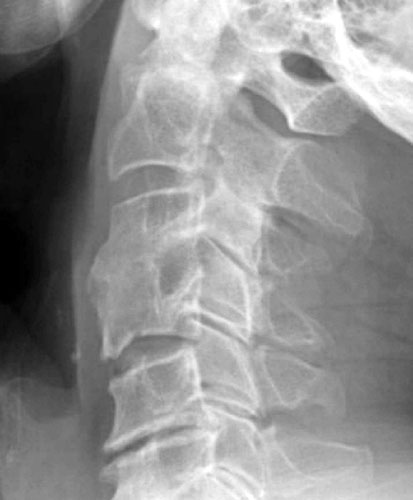

Conservative management utilizing a rigid cervical collar was prescribed for 6

months. 5 months later bony healing has

occurred with incorporation of the graft. |